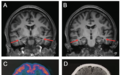

影像学检查:患者脑MRI显示双侧海马体轻度萎缩,脑沟和脑裂轻度增宽。脑 PET 成像显示颞叶皮质的双侧低代谢,无明显淀粉样斑块或异常tau蛋白沉积。MRA未见异常。

A:患者顶叶、颞叶皮质、海马结构轻度萎缩,脑沟增大;B:双侧脉络膜稍增宽,颞角未见明显增大;C:双侧颞叶低代谢;D:轻度萎缩。图源论文